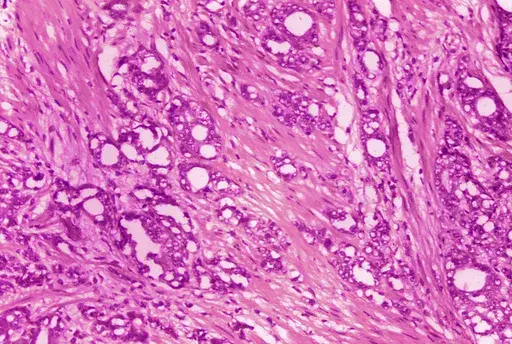

This December 1993 microscope photo provided by the National Cancer Institute shows a typical neuroblastoma with rosette formation. In a study published Wednesday, April 5, 2023, in the New England Journal of Medicine, a novel treatment, CAR-T cell therapy, using supercharged immune cells, appears to work against tumors in children with the rare kind of cancer. (Dr. Maria Tsokos/National Cancer Institute via AP)